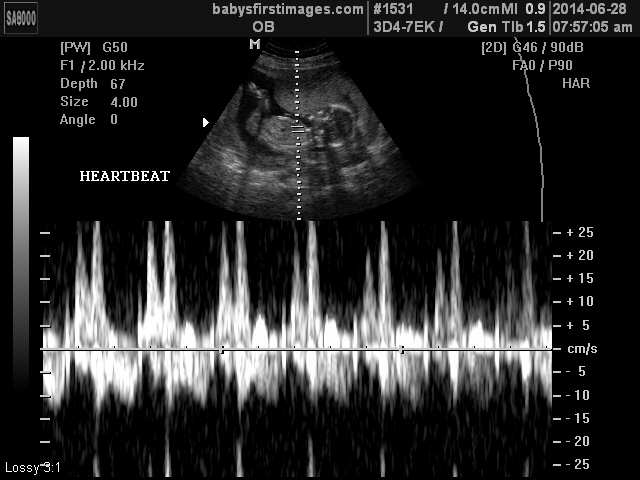

So I’m a couple of days late on the blog update… but it’s official – we’re having a girl! I’m going to steal the words from one of my aunts… I love when God’s plans fit with our desires. Amen! It is such a blessing that we’ll get to experience raising boys and a girl, and I truly feel as though our family will be complete come December. And I am especially excited for my husband because I know how much he wanted a daughter. I can’t wait to see him get to live that dream of having daddy’s little girl – it is going to be awesome!